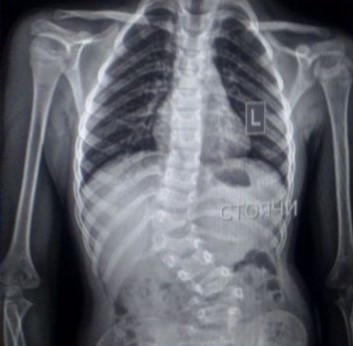

Для Марійки з міста Радивилів це так і є — вона любить літо, обожнює кошенят, захоплюється математикою та малюванням. Але є одна річ, яка з народження обтяжує її життя — сколіоз, який прогресує.

Єдиний шанс зупинити викривлення хребта та уникнути серйозних проблем із внутрішніми органами в майбутньому — складна операція з встановлення спеціальних імплантів.

Дівчинка пройшла всі необхідні обстеження, лікарі готові взяти її на операцію хоч завтра. Але є одне „але“ — імпланти потрібно купити самостійно, держава їх не забезпечує.

Це дуже дороге обладнання. Ціна становить 273 800 гривень.